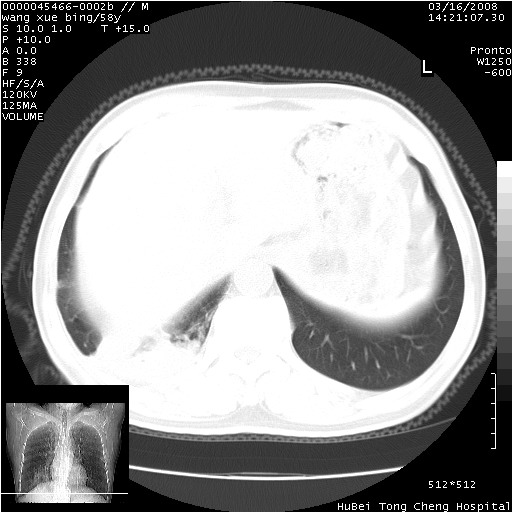

患者 男,58岁。咳嗽、咯血3月余。

胸部ct轴位平扫(层厚10mm,螺距1.5,重建间隔10mm),图像如下:

考虑右下肺中心型肺癌并远端阻塞性炎症及胸膜及纵隔淋巴转移

支持癌性空洞并远端阻塞性炎症